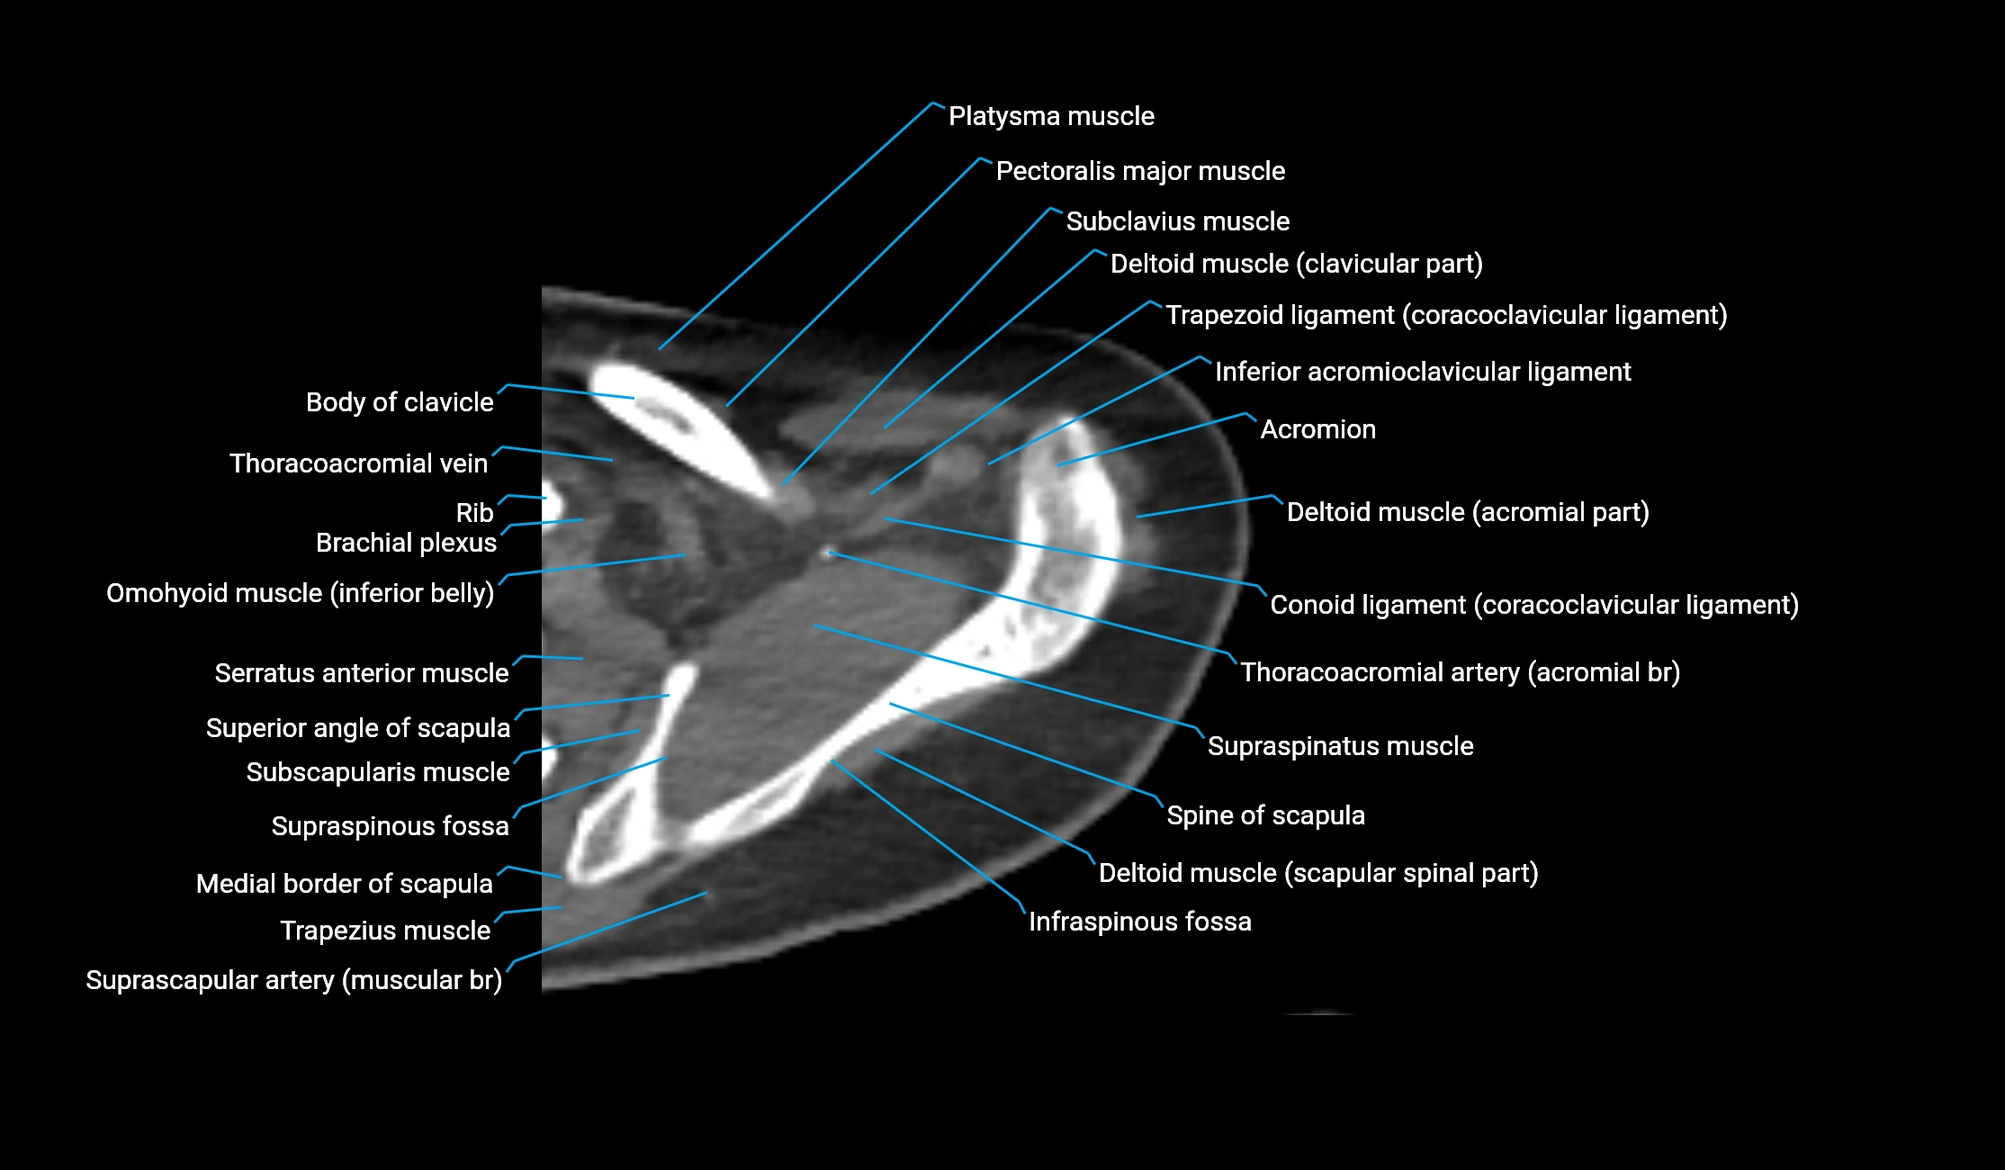

- Acromial part of deltoid muscle

- Acromioclavicular ligament

- Acromion process of scapula

- Brachial plexus

- Clavicular part of deltoid muscle

- Conoid ligament

- Coracoacromial ligament

- Coracoid process of scapula

- Inferior acromioclavicular ligament

- Inferior belly of omohyoid muscle

- Infraspinatus tendon

- Infraspinous fossa

- Joint capsule of elbow

- Medial border of scapula

- Pectoralis major muscle

- Scapular spinal part of deltoid muscle

- Spine of scapula

- Subclavius muscle

- Subscapularis muscle

- Superior angle of scapula

- Supraspinatus muscle

- Trapezoid ligament

- supraspinous fossa of scapula